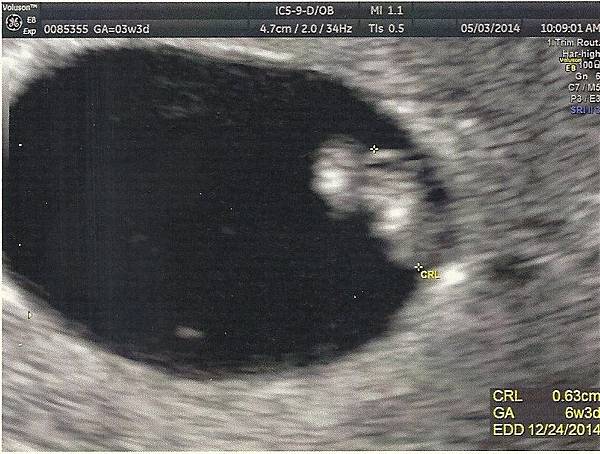

2014.05.03早上10:09

是爸爸和媽媽第一次和妳見面的日子,

今天是星期六媽媽還特地設了鬧鐘,